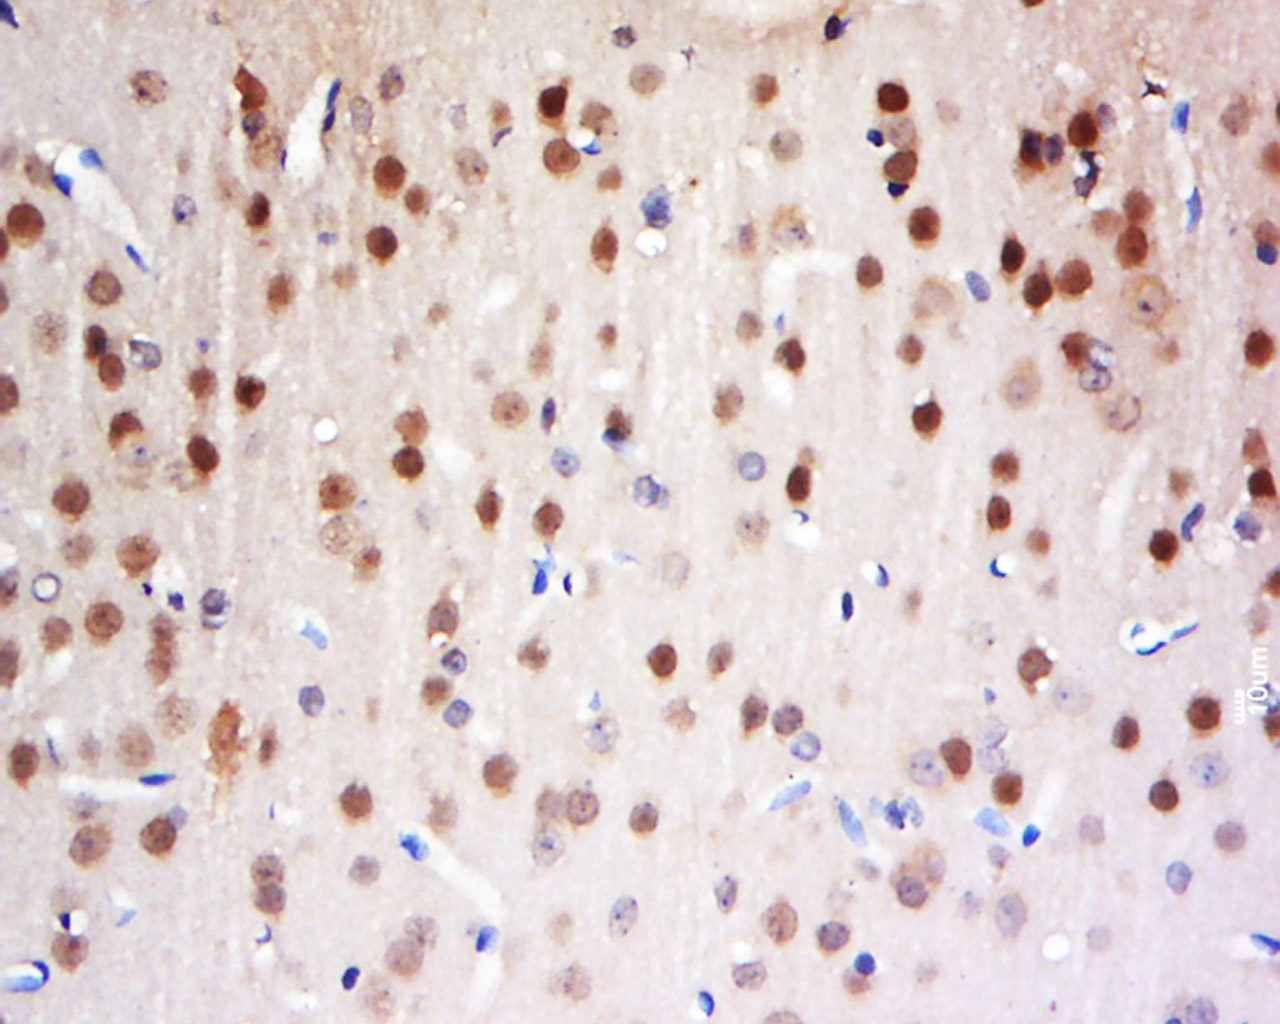

Tissue/cell: Rat brain tissue; 4% Paraformaldehyde-fixed and paraffin-embedded; Antigen retrieval: citrate buffer ( 0.01M, pH 6.0 ), Boiling bathing for 15min; Block endogenous peroxidase by 3% Hydrogen peroxide for 30min; Blocking buffer (normal goat serum,C-0005) at 37℃ for 20 min; Incubation: Anti-FAM13C1 Polyclonal Antibody, Unconjugated(bs-8215R) 1:500, overnight at 4°C, followed by conjugation to the secondary antibody(SP-0023) and DAB(C-0010) staining